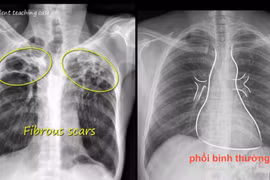

Chăm sóc và theo dõi sau khi hoàn thành điều trị lao thường bị bỏ qua. Sau khi hoàn thành điều trị, mặc dù cơ thể đã tiêu diệt hoàn toàn vi khuẩn lao nhưng vẫn có thể để lại những triệu chứng hoặc di chứng do lao hoặc thuốc.